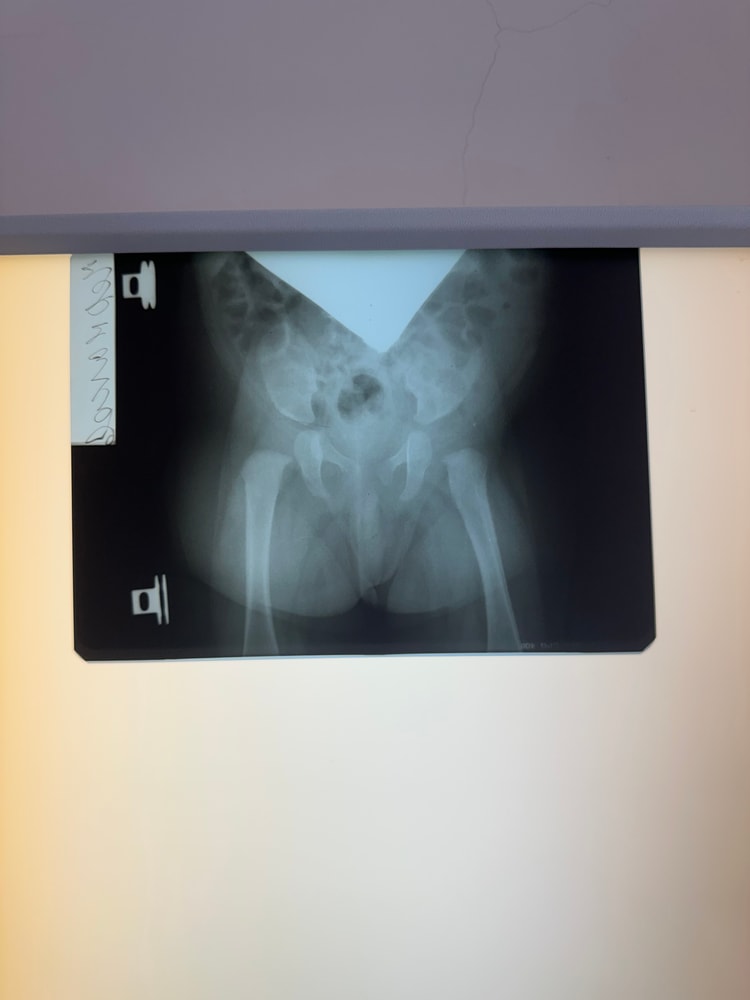

Дисплазия?

Нам по узи поставили дисплазию лёгкой степени,и назначили массаж и электрофорез, сказали ни чего страшного главное во время заметить а у таких маленьких вообще легко убирается) скажут вам и покажут как ножки массажировать, ни чего страшного. Я конечно по снимку ее вижу, и надеюсь что у вас её нет, но если есть все решаемо не расстраивайтесь.

Дисплазию разве не позже ставят, когда ядра окостенения появляются у малышей? Я не эксперт конечно

Нет дисплазии, этот диагноз ставят после 12 мес.